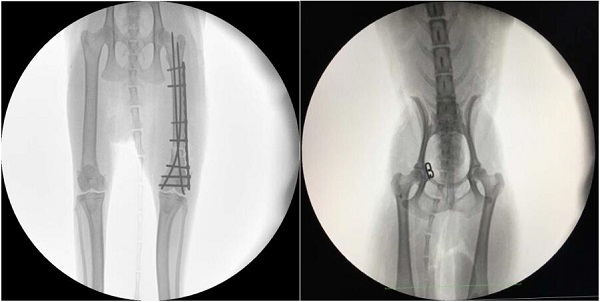

【宠物c臂机临床图像】

- 宠物c臂机

- 设备型号:VET1120